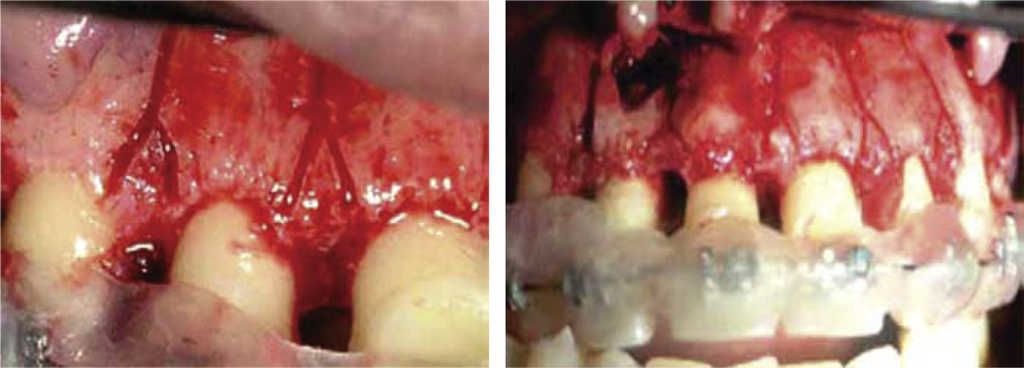

Generson en 1978 modifica la técnica de Köle cambiando la osteotomía supraapical por corticotomía supraapical,2 y describe un método para el tratamiento de mordida abierta utilizando la corticotomía alveolar selectiva conjuntamente con la ortodoncia (Figuras 5 y 6).4

En la figura 6 se observan los cortes verticales sólo sobre la cortical vestibular, unidos con corticotomía horizontal (supraapical) distinguiéndose la penetración en la cortical más fina.